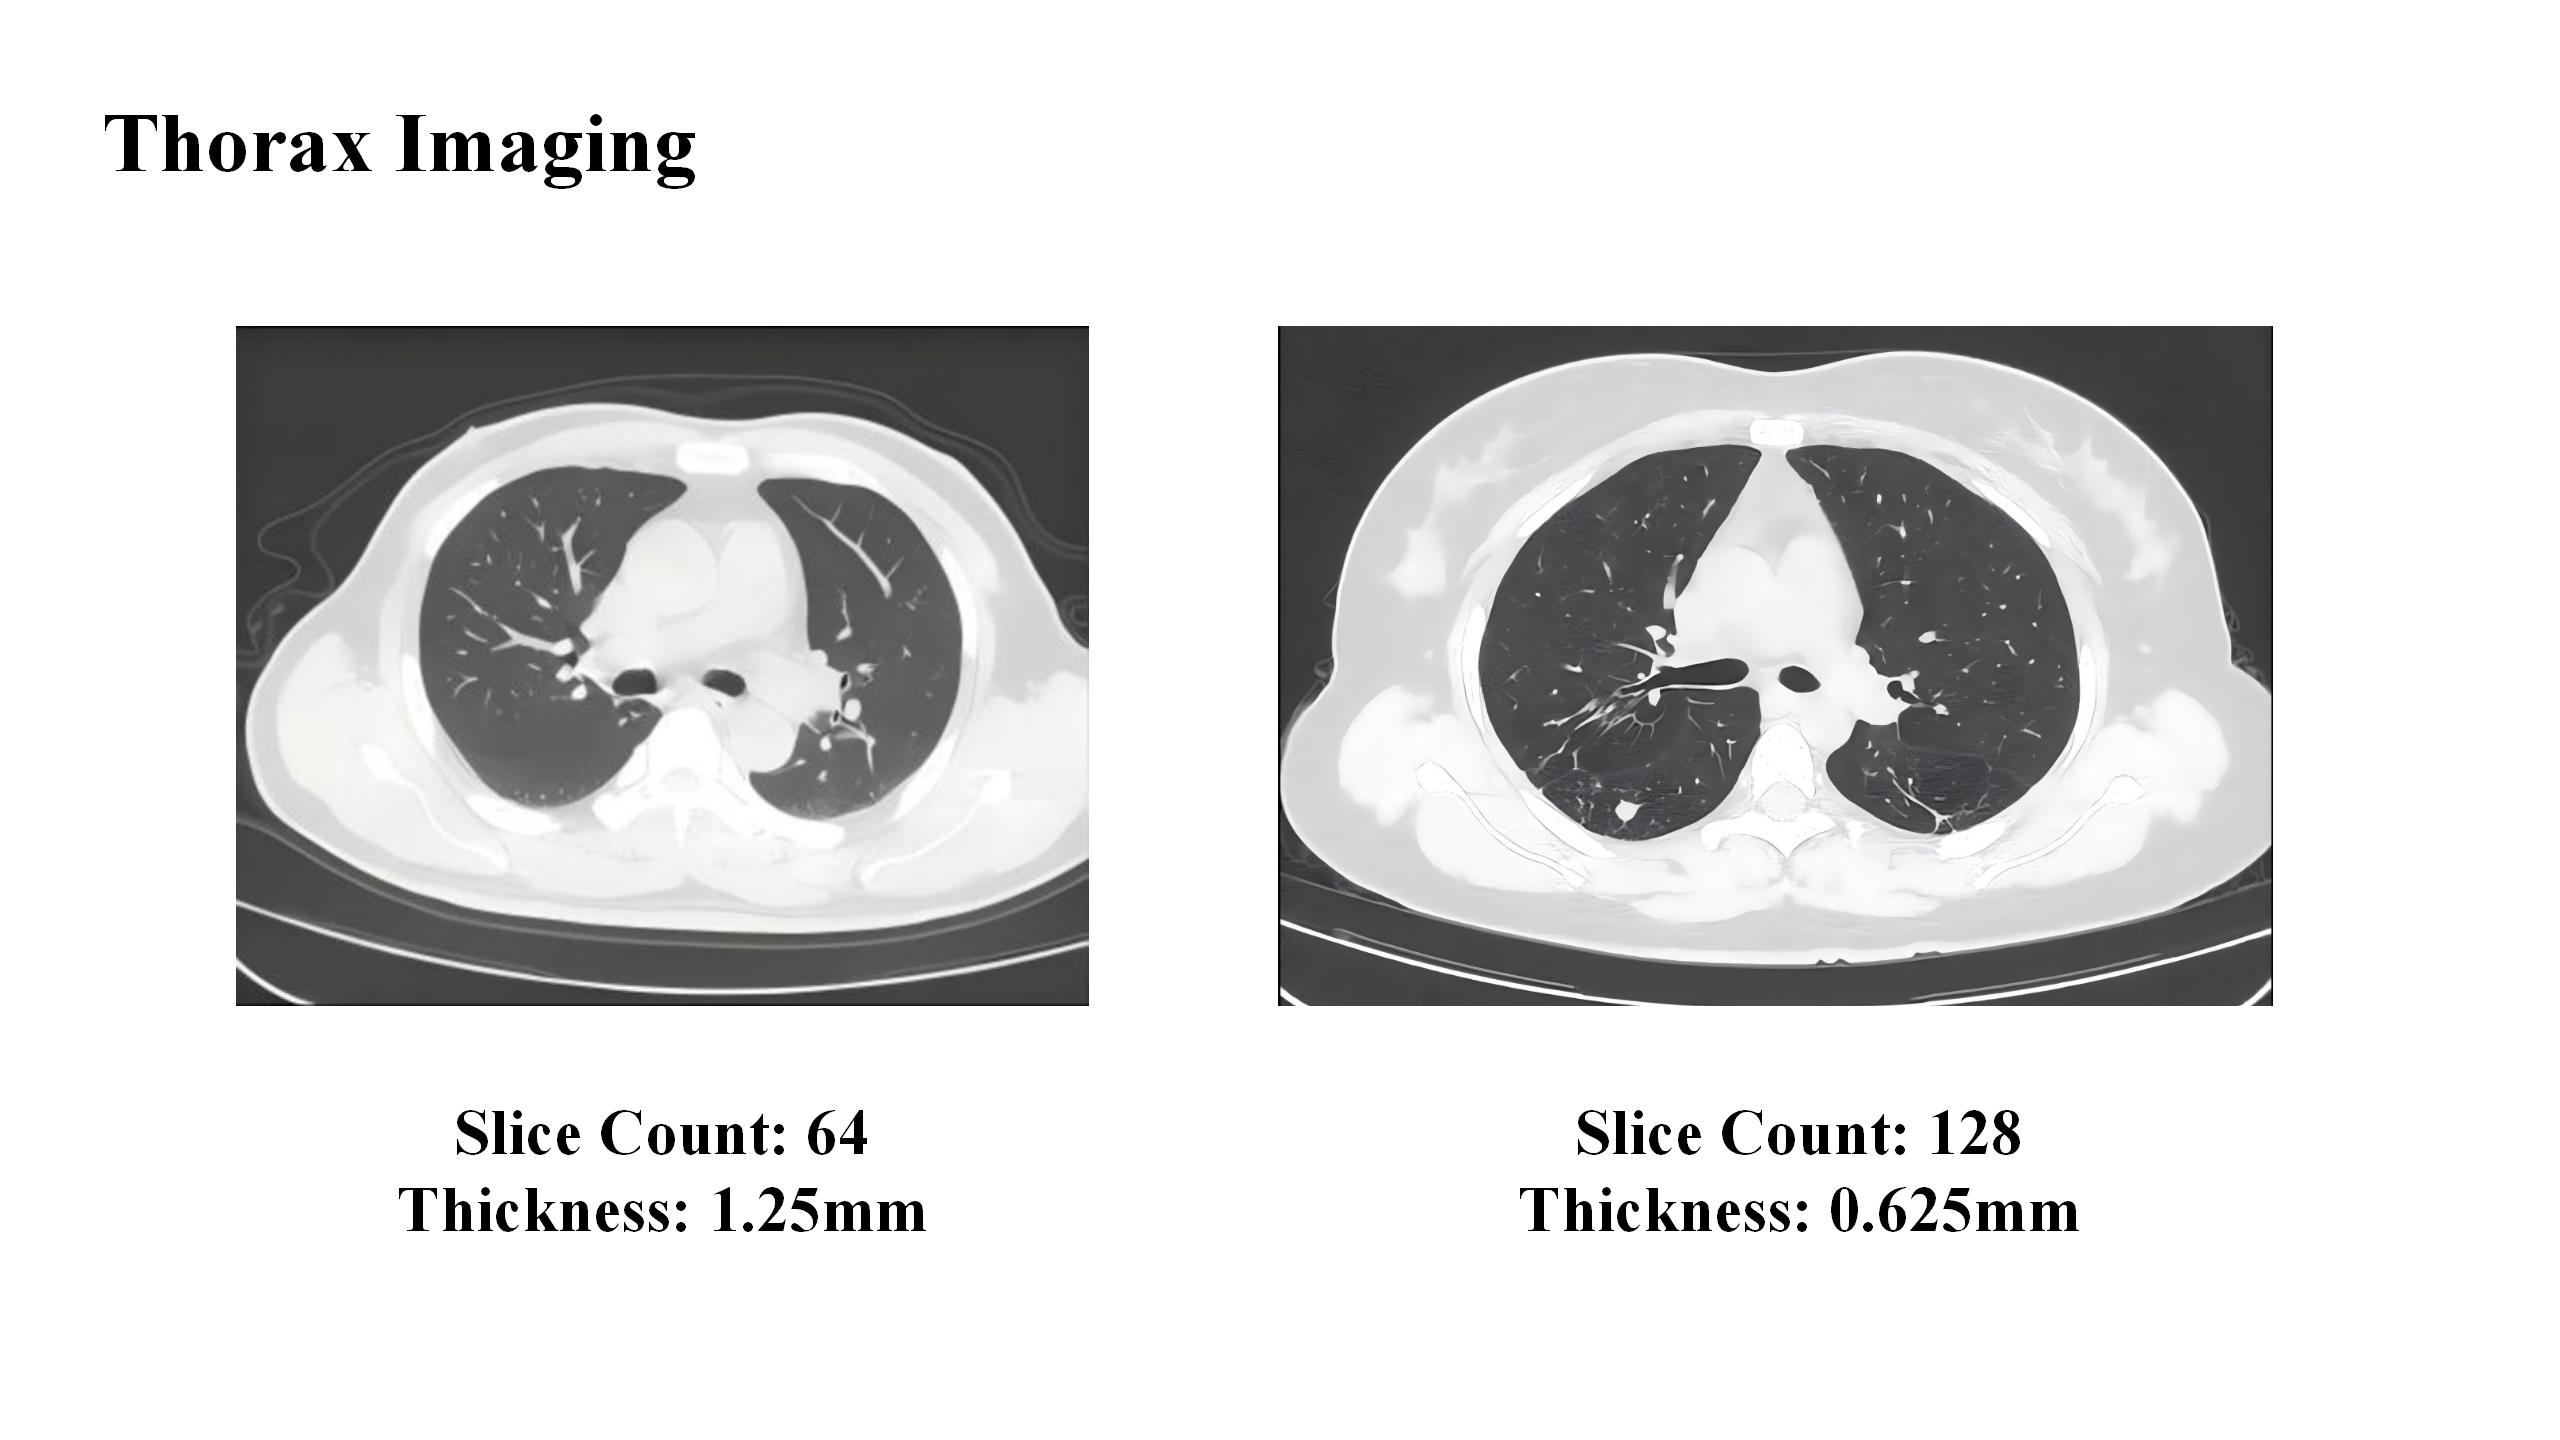

Comparison of Chest CT Image:64-Slice (1.25mm) vs. 128-Slice (0.625mm)

lImage Resolution: With the ability to acquire more slices, the scanner can produce thinner, overlapping images. This is ideal for creating high-resolution, detailed views of fine anatomical structures, such as coronary arteries.